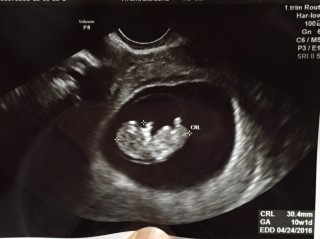

前回のエコーでは10.1ミリで小さくてまだ予定日確定できないねーって先生に言われ、2週間後にエコー撮ったところ30.4ミリに!!順調だねって言ってもらえました(>_<) 手と足を動かしててすごく感動した! 元気に産まれておいで!ぱぱとまま待ってるよ(^_^)

前回はまだ写真をもらえなかったのでこれが初めての写真☆すでに可愛すぎてたまらないよぉ~!! ただ今約3cm。先生も『おっ!元気だねぇ~』と。良かった~ 私のお腹を選んでくれてありがとう。 私の小さな宝石さん☆